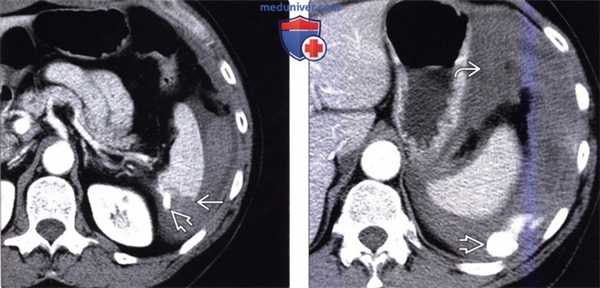

(Слева) На аксиальной КТ с контрастным усилением у женщины 87 лет, получившей травму при падении в доме престарелых, определяется разрыв паренхимы селезенки, а также кровь в брюшной полости наряду с более плотным скоплением жидкости линзовидной формы, неоднородной структуры, сглаживающим выбухающий в норме наружный край селезенки (подкапсульная гематома).

(Справа) На аксиальной КТ с контрастом у мужчины 23 лет, получившего травму в ДТП, визуализируется разорванная селезенка с наличием сторожевого сгустка возле ее края в сочетании с большим количеством крови в брюшной полости. (Слева) На аксиальной КТ с контрастным усилением у юноши 19 лет, пострадавшего в ДТП, во время которого он находился на пассажирском месте и не был пристегнут ремнем безопасности, определяется выраженный гемоперитонеум в верхних отделах брюшной полости, разрыв селезенки с наличием внутри нее псевдоаневризм высокой плотности, а также активная артериальная экстравазация в брюшной полости снаружи от селезенки.

(Справа) На аксиальной КТ с контрастным усилением у этого же пациента определяется активная артериальная экстравазация с распространением крови в левый латеральный канал; «свежая» кровь окружена менее плотной геморрагической жидкостью.